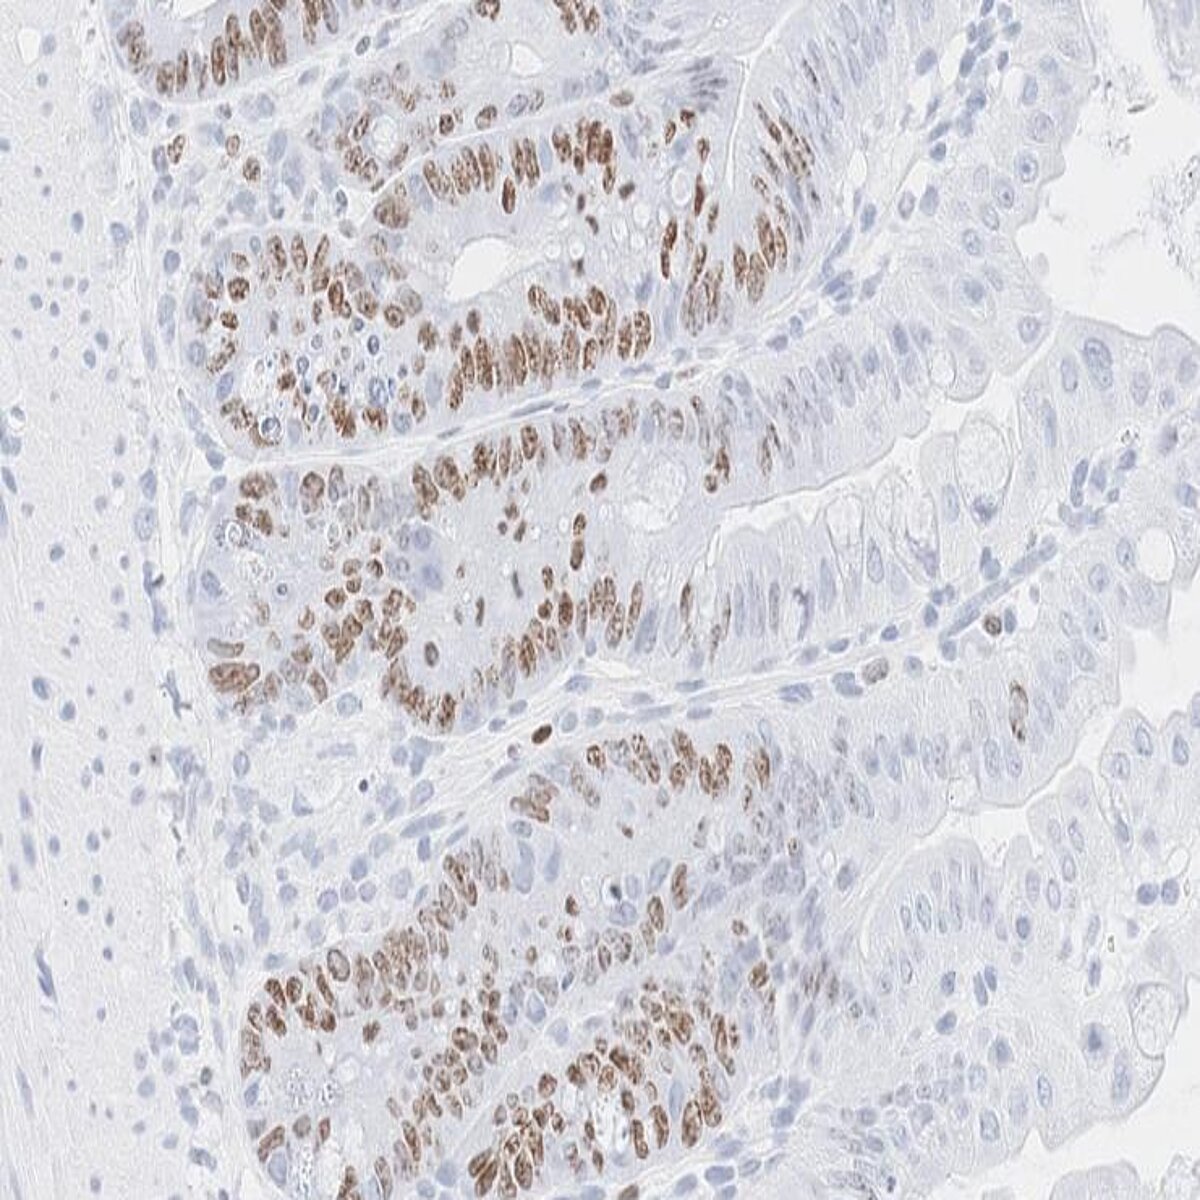

Intestines one week after abdominal irradiation, showing proliferating epithelial cells (in brown) © TUM

PhD student and first author of the study, Sascha Göttert, from the Clinic and Polyclinic for Internal Medicine III at UKR, discovered that in both mouse models and patient samples, Tregs produce two inflammation-associated molecules that work together to stimulate intestinal stem cells: “We found that interferon-gamma (IFNγ) and interleukin-10 (IL-10) act in concert to influence the gut’s natural repair units,” explains Göttert. While IFNγ alone triggers rapid cell growth but exhausts the intestinal stem cell pool, and IL-10 alone provides only weak support, their combination delivers a powerful yet sustainable repair signal. This cooperation supports both rapid healing and long-term regeneration of the gut following immune- and radiation-related injuries, such as after stem cell transplantation or abdominal irradiation.